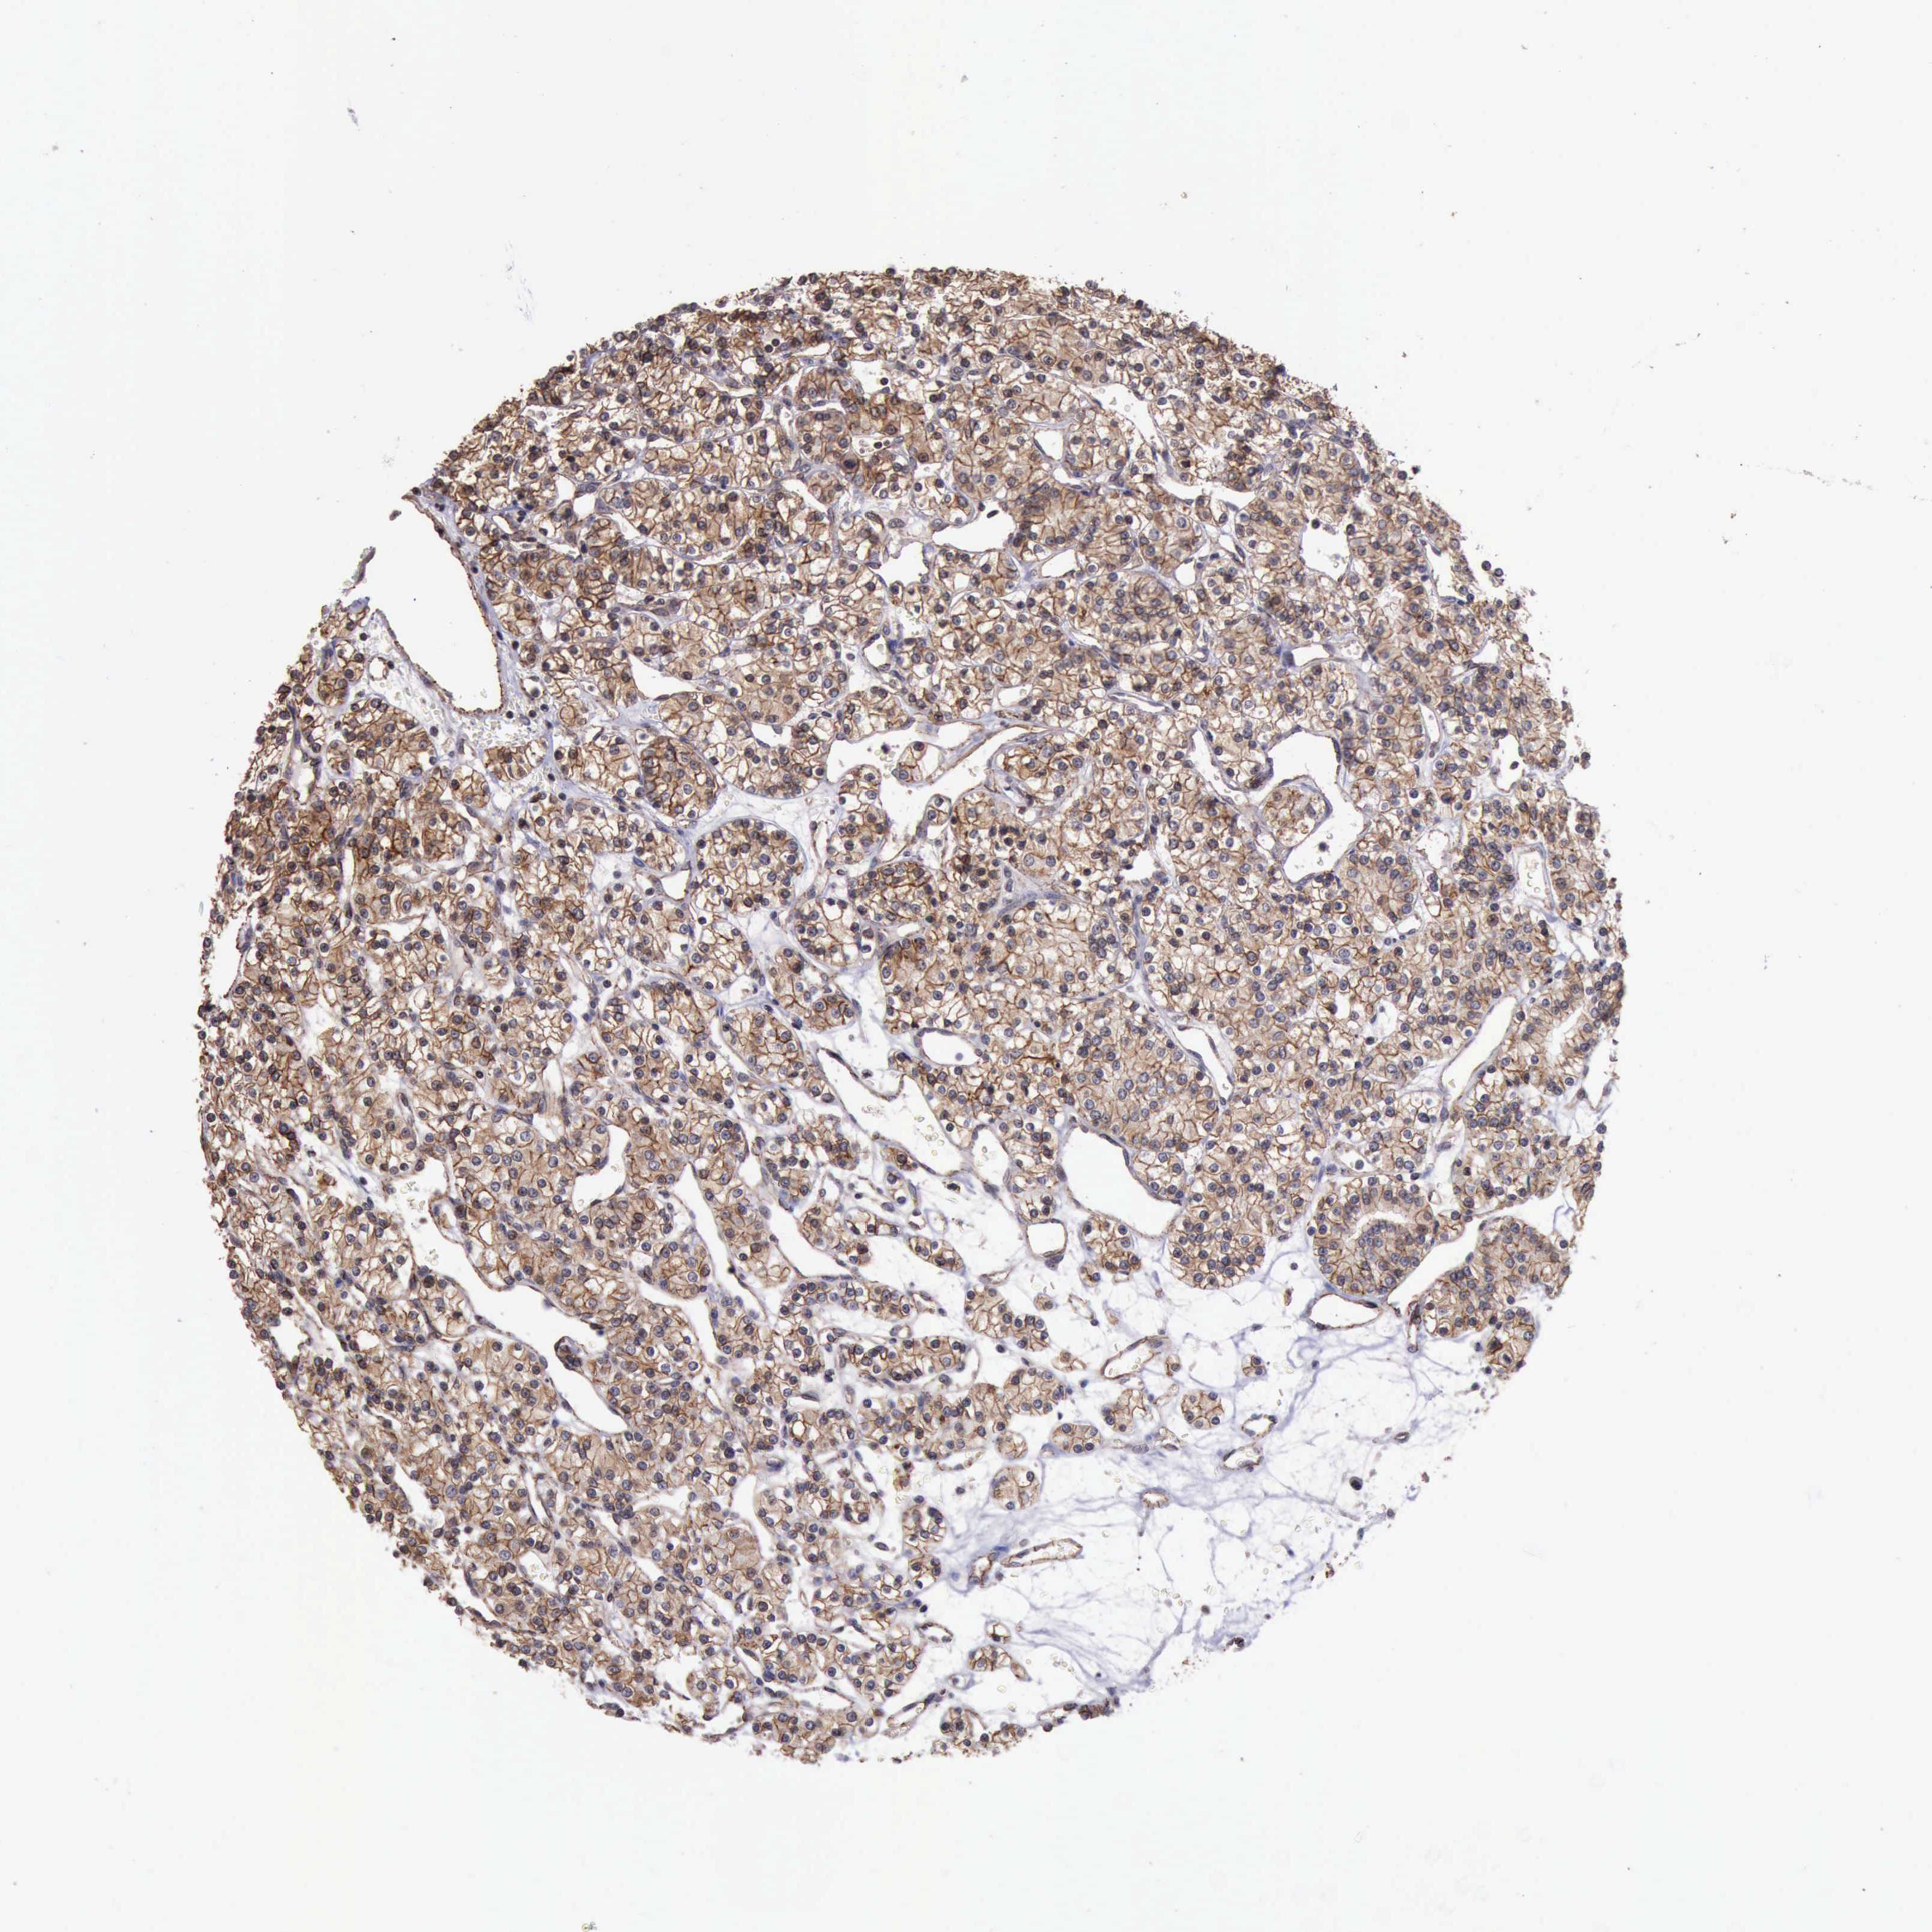

CANCER RENAL CANCER Show tissue menu

KICH TCGA KIRC TCGA KIRC VALIDATION KIRP TCGA PROTEIN RCC CPTAC PROTEIN EXPRESSION